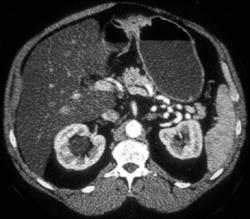

Linitis Plastica